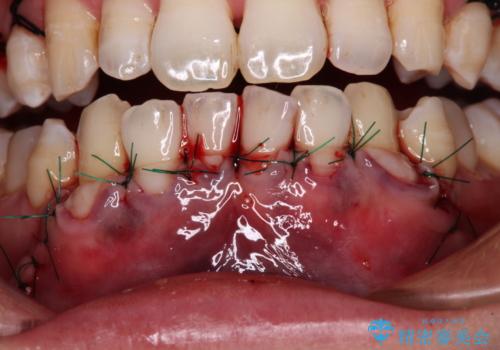

歯肉が菲薄であることが経年的な進行の原因であることが推察されたため、上顎からの結合組織移植術(CTG)により、歯根の被覆を行うとともに、歯肉の厚みを増すことで将来の退縮リスクを抑制することとしました。

上顎両側から歯肉を採取したたため、術後は痛みや出血で辛い思いをされましたが、1回の処置で満足のいく結果となりました。

- 外科手術のため、術後に出血、痛みや腫れ、違和感を伴います